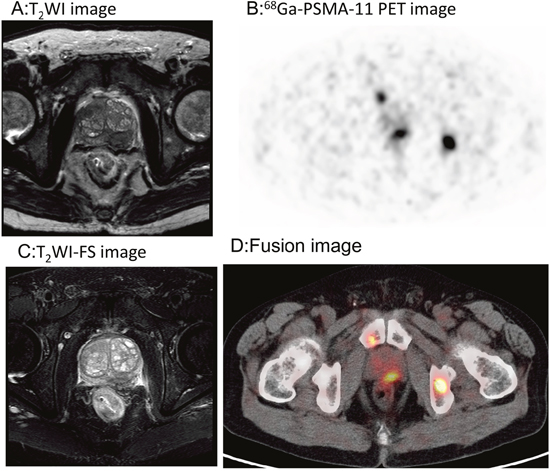

In treatment-naïve PCa patients (Gleason score 6-9), all prostatic primary lesions were PSMA-avid on 68Ga-PSMA-11 images (SUVmax 17.09 ± 11.08). In 4 patients, no extraprostatic lesions were found. One patient who was scheduled with local radical prostatectomy had 3 pelvic lymph nodule metastases in addition to his prostatic lesion. Ten patients with mCRPC were administered androgen depriving and chemotherapy. These patients were not treated with radical prostatectomy due to their advanced stage, with multiple lymph node and bone metastases. The prostatic primary lesions were visualized using high focal uptake (SUVmax 13.33±12.31, n=10). Pelvic MRIs showed a hypo-intensity T2WI signal in the peripheral zone of the cancerous prostate, and some patients exhibited invasion of peripheral organs, including the seminal vesicles.68Ga-PSMA-11 PET/CT enabled precise definition of the prostatic primary lesion and was consistent with the MRI findings. A representative case is shown in Figure 1.

Figure 1: 68Ga-PSMA-11PET/CT versus MRI for the evaluation of the primary prostatic lesions. Focal uptake was found in the left peripheral zone of the prostate gland, which matched the hypointensity signal on MRI. A. T2WI image. B. 68Ga-PSMA-11 PET transverse image. C. T2WI-FS image. D. Fusion image.